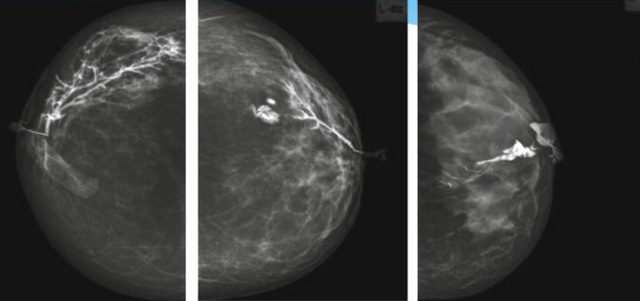

乳腺导管内乳头状瘤分为以下两个,位于乳晕区大导管的中央型乳头状瘤,起源于末梢导管小叶单位的外周型乳头状瘤。外周型乳头状瘤常常没有明显的的临床表现,常因X线或乳腺超声设备检查发现。重点要关注的是中央型乳头状瘤,发生于任何年龄的女性,以40~50岁者居多。它表现为:单侧乳头溢液,特别是血性溢液少数病人可在乳晕区触及肿块。从病理学上面讲表现为导管上皮和间质增生形成有纤维脉管束的乳头状结构。这是它一个病理学上的表现。它的超声表现为:病变导管囊状扩张呈无回声,内可见乳头状低回声或中等回声。乳晕处的导管扩张,管腔内可见边界清楚的,低回声实性结节。外周型导管内乳头状瘤可,表现扩张为为低回声的实性结节,CDFI:部分肿瘤可显示为轴心性的看到血流信号。乳腺增生症:可见导管扩张,内无乳头状实性回声,导管内乳头状癌:囊内乳头状癌病变较大,不规则,厚基底,血流丰富。以囊性为主的混合回声,形态不规则,内见实性低回声实性低回声可见少量血流,病理为囊内乳头状癌。

乳腺超声设备检查的价值在哪里呢?它可以检查发现乳晕周围的各种病变,对于单侧乳头溢液、血性溢液的患者,超声是首选的影像学检查方法。注意:导管内乳头状瘤可合并不典型增生或,导管内乳头状癌,手术前怀疑时候,就应该手术切除而不是用微创手术。